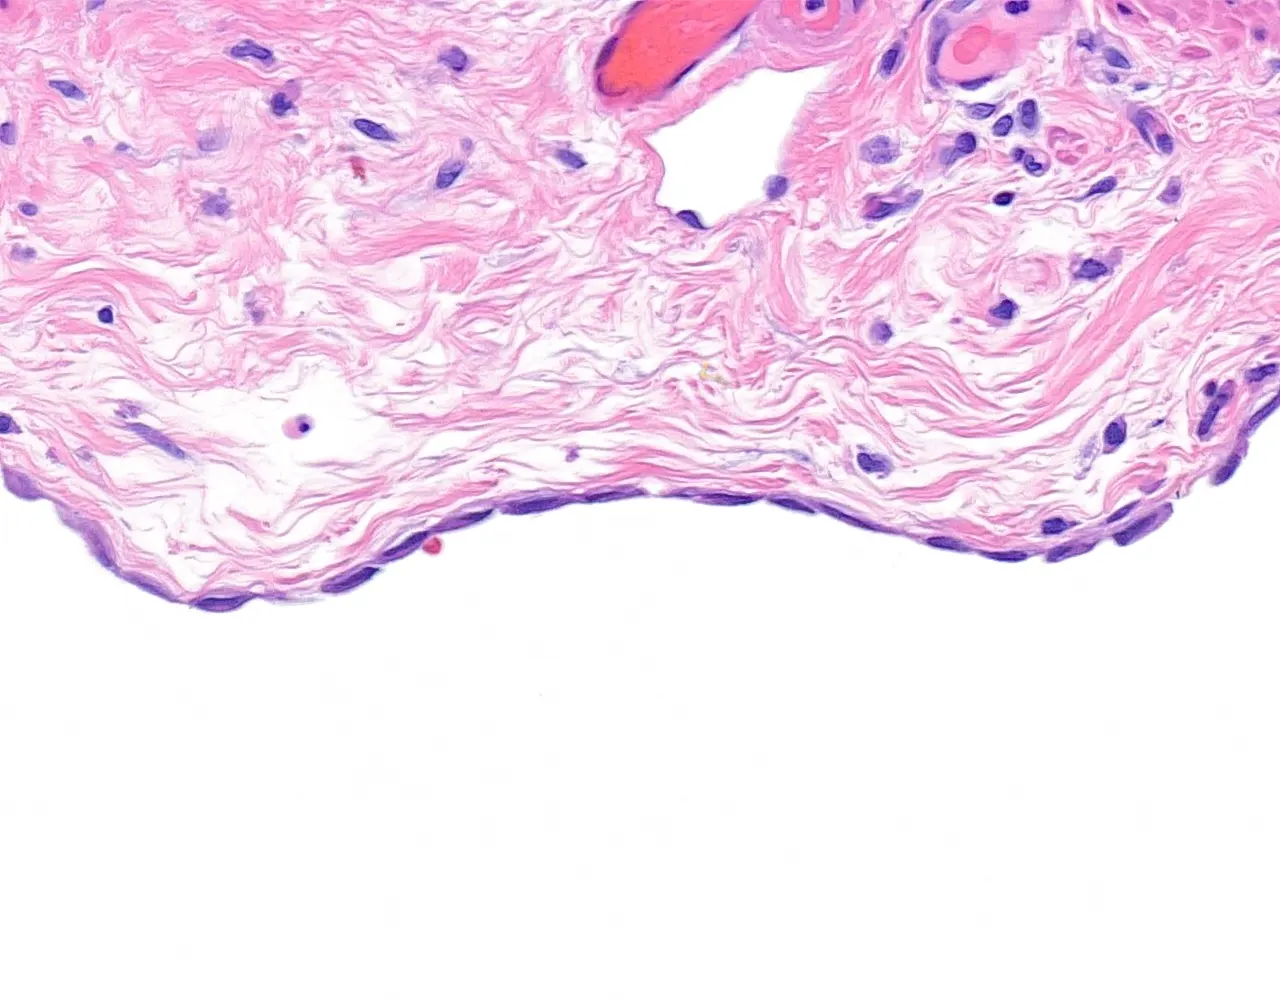

- Le côlon ascendant et le côlon descendant sont majoritairement rétropéritonéaux, alors que le côlon transverse et le côlon sigmoïde sont intrapéritonéaux et recouverts par la séreuse.

- Le rectum est partiellement recouvert par une séreuse dans sa portion proximale, le reste du rectum est entouré par une adventice.